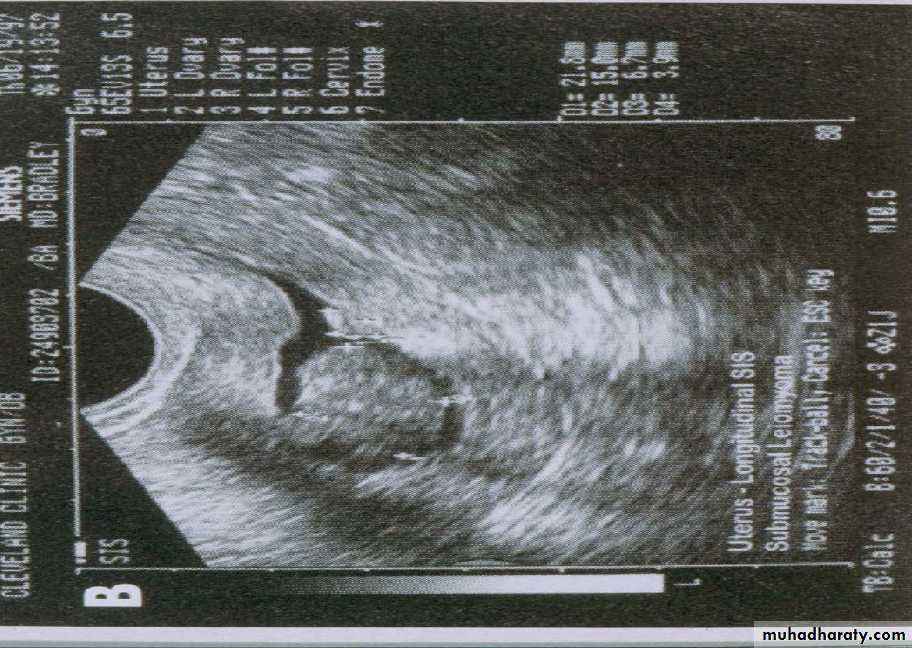

A refinement of vaginal probe ultrasound is saline infusion sonography (SIS). A salt water (saline) solution is injected into the uterus with a small tube (catheter) before the vaginal probe is inserted. The presence of liquid in the uterus helps make any structural abnormalities more distinct. These two non-invasive procedures cause less discomfort than endometrial biopsies and D & Cs, but D & C still remains the definitive test for diagnosing uterine cancer.